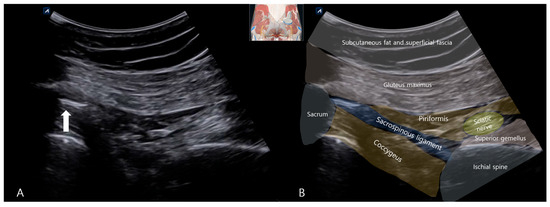

Background: Deep gluteal syndrome (DGS) is an underdiagnosed cause of sciatica-like pain, involving the entrapment of the sciatic nerve by various structures within the subgluteal space. While cases of ossification or calcification in the context of severe pelvic imbalance have been rarely reported, isolated SSL calcification as a primary cause of DGS remains largely unexplored and undocumented. This case report presents the first documented instance of sacrospinous ligament (SSL) calcification identified as the primary cause of DGS and its successful management with ultrasound-guided prolotherapy. Case Presentation: A 51-year-old female presented with severe, worsening left-sided sciatica of several months’ duration. Physical examination revealed an antalgic gait, positive sacroiliac joint tests, and multiple positive DGS-specific provocative tests (FAIR, Pace sign, Seated Piriformis Stretch). Radiographs and musculoskeletal ultrasound (MSK-US) confirmed calcification within the left sacrospinous ligament, with associated sciatic nerve swelling. The patient underwent three sessions of ultrasound-guided prolotherapy (dextrose 10% with lidocaine) targeting the calcification site, followed by a structured rehabilitation program. Results: The patient reported a significant reduction in pain, from a Visual Analog Scale (VAS) score of 10/10 to 1/10 within one month. All previously positive provocative tests converted to negative, indicating a resolution of the nerve entrapment. Functional mobility was fully restored. Conclusions: This case highlights isolated sacrospinous ligament calcification as a potential and previously overlooked pathological entity responsible for deep gluteal syndrome. To our knowledge, this is the first report to implicate ligamentous calcification as a primary etiological factor in DGS. Musculoskeletal ultrasound proved indispensable for both diagnosis and treatment guidance. Furthermore, ultrasound-guided prolotherapy emerged as a successful and minimally invasive therapeutic option in this case, potentially by stabilizing the ligament and reducing neurogenic inflammation. This case expands the differential diagnosis of sciatica, introduces a new target for intervention in refractory cases, and underscores the need for future studies in larger patient cohorts to validate these findings. Full article

Figure 1